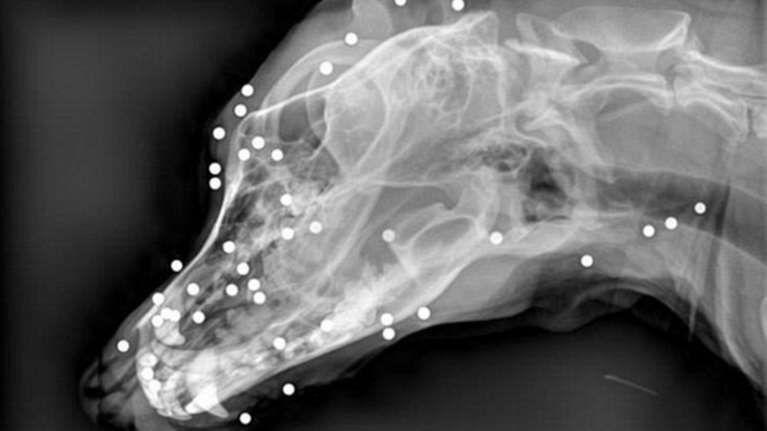

Σοκ με κακοποίηση σκύλου στην Κρήτη: Πυροβόλησε το άτυχο ζώο με καραμπίνα στο πρόσωπο

Σοκάρει η κακοποίηση σκύλου στην Κρήτη με κάτοικο να το πυροβολά με καραμπίνα στο πρόσωπο